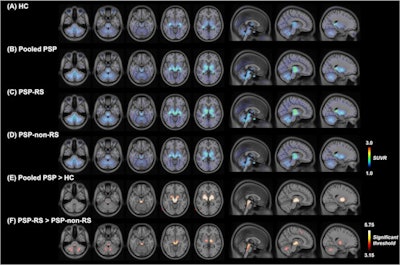

F-18 Florzolotau PET images of patients with progressive supranuclear palsy. The images illustrate F-18 Florzolotau uptake in the healthy control (HC) group (panel A), entire patient cohort (panel B), as well as in the PSP-Richardson's syndrome (RS) (panel C) and PSP-non-RS (panel D) groups. Compared with the HC group, patients with PSP showed significantly increased binding mainly in the pallido-nigro-luysian axis (panel E). While the patterns of tracer accumulation were similar in the two patient groups, the binding intensity was markedly lower in patients with PSP-non-RS (panel F). The color bars in panels A-D indicate standardized uptake value ratios (SUVR), whereas the color bar in panels E-F denote threshold values from the voxel-wise comparisons. Image and caption courtesy of the European Journal of Nuclear Medicine and Molecular Imaging through CC BY 4.0.Liu's team sought to confirm findings from these preclinical studies in a large group of patients using PET imaging with F-18 Florzolotau, a tracer originally developed in 2020 that has shown promise for detecting hallmark tau pathology in Alzheimer's disease. To do so, the investigators recruited 148 consecutive patients with PSP to undergo F-18 Florzolotau PET imaging between May 2019 and January 2022. Twenty subjects with a negative history for neurological or psychiatric disorders were included in a control group for comparison. The researchers tracked 18 subcortical regions of interest and eight cortical regions of interest.

Based on standard radiotracer uptake measurements, the distribution patterns of F-18 Florzolotau uptake in the regions of interest showed a striking similarity to those reported in postmortem studies, with the binding intensity of the tracer to its tau target markedly higher in PSP-/Richardson's syndrome, the classic type of PSP. The tracer also detected tau accumulation at earlier stages of the disorder compared with postmortem immunostaining findings, they noted.